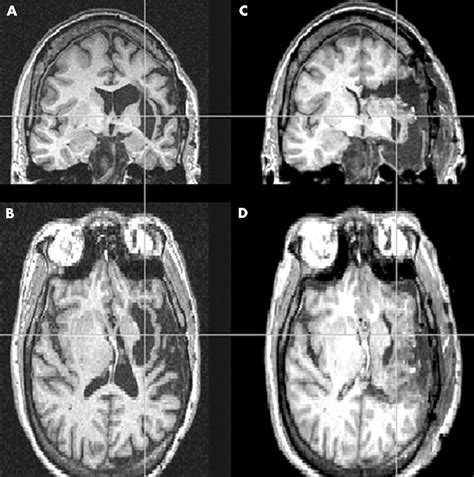

When a radiologist identifies volume loss, they usually assess the distribution of the atrophy. Generalized atrophy refers to widespread loss across the entire brain, while focal atrophy suggests that specific areas, such as the hippocampus or the frontal lobes, are being disproportionately affected. The following table provides a snapshot of how medical professionals categorize these findings:

Asymmetric Loss Often seen in post-stroke changes or specific dementias.

Technological advancements in "volumetric MRI analysis" now allow doctors to quantify brain volume more precisely than in the past. These automated programs can compare a patient's brain size to normative databases, providing a more objective measure of whether the observed loss is truly abnormal for the patient's specific age and biological sex.